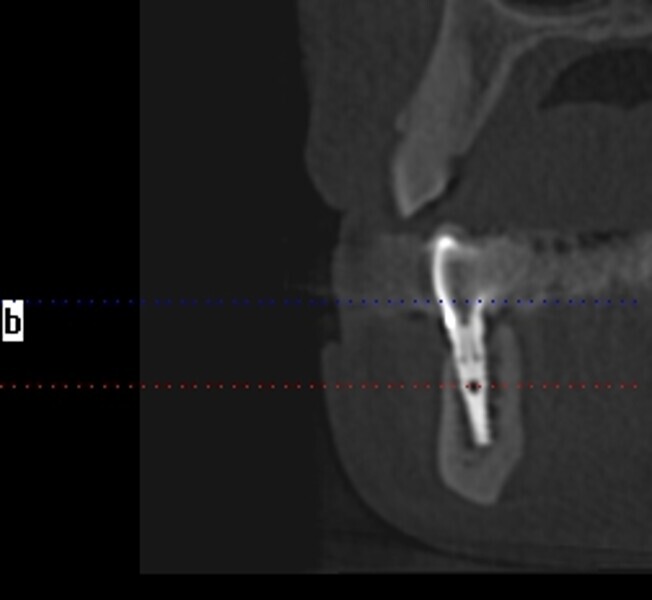

Natychmiastowa implantacja i zaopatrzenie protetyczne pacjentów z zaawansowaną chorobą przyzębia